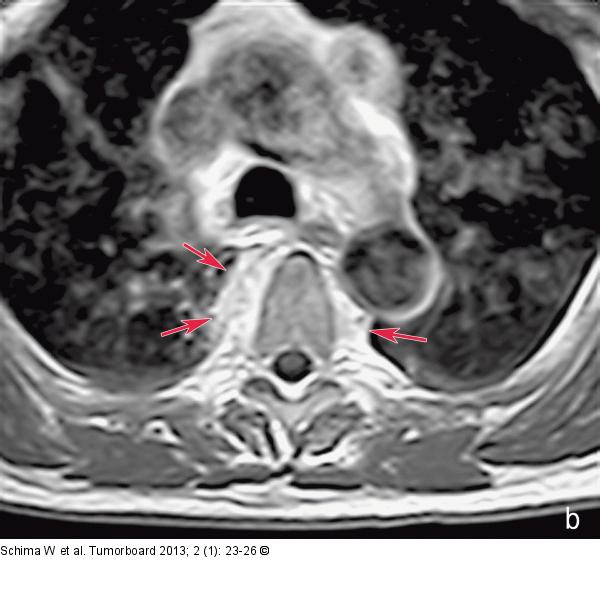

Abbildung 2a-b: Skelettmetastasen MRT der BWS: (a) Es finden sich in der STIR-Sequenz Veränderungen in der Bandscheibe Th 4/5 und ein ausgeprägtes Ödem in den angrenzenden Wirbel Th 4 und 5. (b) Die Kontrastmittelverstärkte Sequenz zeigt einen paravertralen Weichteilanteil (Pfeile), was auch typisch für eine Spondylodiszitis ist |

MRT der BWS: (a) Es finden sich in der STIR-Sequenz Veränderungen in der Bandscheibe Th 4/5 und ein ausgeprägtes Ödem in den angrenzenden Wirbel Th 4 und 5. (b) Die Kontrastmittelverstärkte Sequenz zeigt einen paravertralen Weichteilanteil (Pfeile), was auch typisch für eine Spondylodiszitis ist |